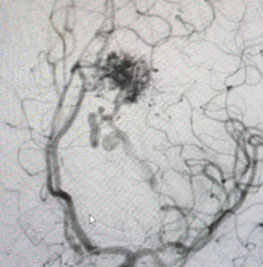

Head CT was consistent with a small acute left intraventricular hemorrhage (Figure 1).

Fig. 1